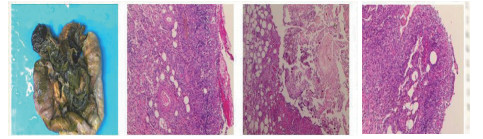

| 图 1 全腹CTA(2017-12-22):门静脉及肠系膜上静脉血栓形成 |

1 资料与方法患者男,30岁,因“腹胀、腹痛6 d,高热1 d”于2017年12月11日由广州南沙区中心医院转诊收入中山大学孙逸仙纪念医院全科医学科。患者本次起病前无明确病因或明显诱因。患者以左上腹轻微胀痛起病,进行性加重。南沙区医院查血常规:白细胞14.27×109/L,血小板50×109/L,中性粒细胞比例74.5%,嗜酸粒细胞1.02×109/L,嗜酸粒细胞比例7.2%。全腹CT+CTA提示:门静脉左右主干及其小分支栓子形成。后在3 d内连续复查血常规,提示血小板进行性下降,由50×109/L相继降至35×109/L、18×109/L;(嗜酸粒细胞计数及比例未能提供),并出现高热(体温39.5℃),因病情危重,遂转诊本院。入院时患者精神疲乏、高热,腹部胀痛难忍,伴有咳嗽。查体:体温38.6℃,心率87次/min,血压102/76 mmHg,指尖血氧饱和度90%~91%。双肺呼吸音粗,双肺均可闻及小水泡音。腹部稍膨隆,叩诊鼓音,左上腹及脐周轻压痛,无反跳痛。听诊肠鸣音减弱,约1~2次/min。当天查血常规示白细胞11.85×109/L,血小板23×109/L,中性粒细胞比例58.1%,嗜酸粒细胞3.5×109/L,嗜酸粒细胞比例29.5%。凝血常规提示:PT 15.9S,PTA 51.1%,PT/R 1.39,Fbg 1.59 g/L,PTINR 1.39,APTT 35.2 s,D-二聚体114.36 mg/L FEU(参考值范围0~0.55 mg/L FEU)。胸部+全腹部CT+CTA示“门静脉主干及左、右支、肠系膜上静脉近端栓子形成;腹主动脉及左侧髂总动脉小附壁血栓;左肺上叶尖后段、左肺上叶下舌段、右肺中叶及双肺下叶炎症;乙状结肠两段节段性管壁增厚,建议排外占位性病变;腹水、盆腔积液,大网膜炎性病变可能性大”。每日复查血常规,发现血小板进行性下降,最低至15×109/L(参考值范围125~350×109/L),嗜酸粒细胞计数及比例进行性升高,分别达到8.07×109/L(参考值范围0.020~0.52×109/L)和51.1%(参考值范围0.4-8.0%)。每日复查凝血常规亦提示凝血指标不断恶化,纤维蛋白原最低降至0.63 g/L。在予禁食、“美平(美罗培南)”抗感染、输注纤维蛋白原及血小板、维护水电解质平衡及营养支持的积极治疗的同时,还积极完善了以下检查寻找病因:①血液系统方面:血浆鱼精蛋白副凝实验:阳性(+);凝血功能实验:PT 15.5S↑,PTA 47.8%↓,PT/R 1.35↑,PTINR 1.36↑,APTT 40.4 s↑,AT-Ⅲ 57.7%↓,F-VII 32.8%↓,F-Ⅷ 68.1%↓,F-X 68.0%↓,F-XII 24.0%↓;纤维蛋白降解产物:381.4 mg/L↑;血栓弹力-血小板图:R时间10.3 min↑;角度18.5度↓;最大血块强度13.2 mm↓;MA(ADP)值5.6 mm↓。骨髓病理学:嗜酸性粒细胞增多(43%),巨核细胞减少(7个)。慢淋/淋巴瘤表型分析:获取和分析细胞数5.0万;粒细胞区百分比82.6%;淋巴细胞区百分比9.4%;单核细胞区百分比2.0%;CD45dim细胞区百分比1.3%;有核红及细胞碎片区域百分比4.6%。ETV6/PDGFRB融合基因、FIP1L1/PDGFRA融合基因(—)。骨髓细胞学病理结果:符合嗜酸细胞增多症;②消化系统检查:大便细菌培养鉴定及药敏提示无志贺、沙门菌生长,有真菌生长;大便难辨梭菌毒素检测(—);粪便找寄生虫、找阿米巴、寄生虫七项均为(—);消化肿瘤系列提示CA-125 244.8 U/mL↑;腹腔穿刺术穿出“血性腹水”,腹水CA-125 1006.0 U/mL↑,腹水找癌细胞(—);复查腹部CT+CTA:乙状结肠两段节段性管壁增厚,建议进一步检查;排外占位性病变;遂行PET-CT:提示全身未见明确恶性征象。行电子结肠镜示:内镜诊断:(1)回肠末段炎症;(2)乙状结肠炎症;(3)内痔。钳取组织送病理,提示:标本①(回肠末端)黏膜组织呈慢性炎,伴糜烂,一些嗜酸性粒细胞浸润(约35个/HPF);②(乙状结肠)黏膜组织呈慢性炎,伴糜烂,个别嗜酸性粒细胞浸润(约4个/HPF)。③风湿免疫系统方面:免疫八项、风湿四项:C反应蛋134.0 mg/L,余未见异常;总IgE 170 IU/mL↑;抗ENA抗体、狼疮两项、血管炎两项、免疫球蛋白G4、抗心磷脂抗体三项均为阴性;④其他感染病原学检查:乙肝、肝炎系列、性病三项、痰找抗酸杆菌、T-spot实验、流行性出血热、登革热抗体、登革热病毒NS1抗原、外斐氏试验、肥达氏试验、痰结核培养、骨髓培养、血液细菌、血液厌氧菌培养均为阴性。经过上述检查,初步考虑“特发性嗜酸性细胞增多症”,于12.15开始予“甲泼尼松龙40 mg静滴, 1次/d”及“低分子肝素0.6 ml皮下注射, 1次/d”抗炎抗凝治疗。患者病情及检验指标有所好转,热退、腹胀减轻,血常规提示血小板升至49 ×109/L,嗜酸粒细胞计数和比例均下降至正常,凝血常规提示D-二聚体降至47.90 mg/L FEU。但12-22患者自行进食多量米饭后突发腹胀痛较前加重,急查血常规提示白细胞升至21×109/L,血小板再次下降至15×109/L,D-二聚体升至97.28 mg/L FEU,全腹CTA提示“门静脉主干及左、右支、肠系膜上静脉近端新发栓子形成”,遂于当日转至ICU予“尿激酶20万U+肝素钠1250 U”溶栓治疗后予“低分子肝素0.6 ml皮下注射, 1次/12 h”序贯抗凝治疗。后患者病情渐渐稳定,至2018-1-18患者在“甲泼尼松龙12 mg口服, 1次/d”及“立伐沙班20 mg口服, 1次/d”的维持治疗下,血小板、嗜酸粒细胞计数及纤维蛋白原均回复正常,D-二聚体下降至3.52 mg/L FEU。但遗憾的是,此时患者再次进食大量米饭,约1 h后突发腹痛、气促,急行胸片+腹平片提示:“双侧膈下游离气体,考虑胃肠道穿孔可能;双下肺少许炎症,少量胸腔积液;腹部多量积气伴肠腔扩张”。遂即送手术室行全麻下“腹腔镜探查+坏死空肠切除+大网膜切除+肠系膜上动脉探查+空回肠双腔造口术”,术后病理提示标本①(大网膜)脂肪组织,部分坏死,合并慢性炎,伴一些中性粒细胞浸润,较多泡沫样组织增生,未见明确血栓,未见恶性改变。②(部分空肠)肠壁组织,部分肠壁全层坏死,合并慢性炎,肉芽组织增生,未见明确血栓,未见恶性改变。免疫组织化学:CD38浆细胞(+)、IgG(+)、IgG4(﹣)。术后继续予“立伐沙班10 mg/d”和“甲泼尼松龙8 mg/d”口服治疗,并于2018.2.4停用“甲泼尼松龙”。2.28复查全腹CTA,仍可见“脾静脉新发血栓,门静脉及肠系膜上静脉血栓较前好转”。3.20行空回肠双腔造瘘管泛影葡胺造影术提示“双腔造瘘管通畅,右中下腹小肠蠕动尚可,结肠各段及直肠通畅,未见对比剂外漏征象”。但患者合并了严重的短肠综合征,致严重低钾低钠血症和继发的代谢性脑病,病情再度转危。继续纠正电解质紊乱、补充营养,最终病情好转后于4.11行“造瘘口回纳修补术”。随访半年,患者仍口服“立伐沙班10 mg/d”抗凝治疗,复查血常规、凝血常规等各项指标均正常,但营养状况较差。